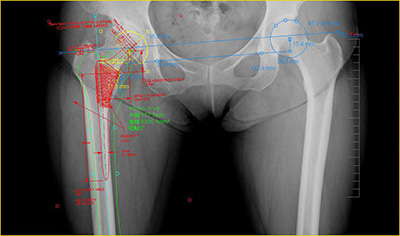

デジタル・プランニングツール”OrthoPlannerPro”は国内外メーカの豊富なインプラントデータと整形外科専門計測を搭載し,整形外科分野のスムーズな完全フィルムレスを実現します。新製品として自動テンプレート配置機能,自動骨切機能等,これまでの製品販売経験を活かし,迅速かつ正確な整形外科のプランニングフローに対応したソリューションを提供します。是非現地でその機能をご覧ください。

展示製品

・整形外科デジタル・プランニングツール“OrthoPlannerPro”